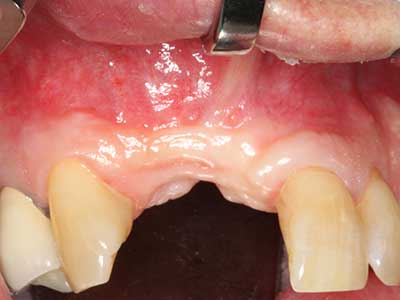

Indicazione: incisione ossea

Il tessuto osseo non è semplicemente una struttura minerale, ma contiene anche una percentuale significativa di fibre di collagene. Ciò significa che non possiede solo una buona forza di compressione, ma anche un certo livello di flessibilità che è possibile sfruttare durante l'esecuzione degli accrescimenti di osso. Nella procedura di espansione classica con incisione ossea, la cresta alveolare atrofizzata viene incisa longitudinalmente ed espansa con cautela dopo aver raggiunto una profondità di osteotomia adeguata (figg. 13-16), idealmente senza una sostanziale rimozione del periostio (Brugnami, Caiazzo et al. 2014, Stricker, Fleiner et al. 2014). I sistemi a piastra e vite con distanza di espansione incrementale si sono dimostrati efficaci nella separazione delle due lamelle ossee restando al di sotto della soglia di frattura. In generale, sono richieste larghezze dell'osso residuo di almeno 3-4 mm (Chiapasco, Zaniboni et al. 2006) per garantire un'adeguata flessibilità e una copertura sufficiente dell'osso per gli impianti futuri. Se necessario, un'osteotomia di rilascio verticale su uno o più lati può migliorare la flessibilità. Una combinazione con ulteriori tecniche di accrescimento, in particolare dal lato buccale, è stata descritta come un'alternativa alla tecnica classica.

La procedura di incisione è particolarmente atraumatica e non comporta una perdita significativa di dimensione durante l'utilizzo delle seghe piezoelettriche, così come non si notano differenze rilevanti tra impianti in mandibole incise e impianti in una cresta alveolare senza deficit osseo (Chiapasco, Zaniboni et al. 2006, Danza, Guidi et al. 2009). Una sufficiente irrigazione continua è essenziale, tuttavia, in particolare con incisione profonda e localmente ristretta, per prevenire la sollecitazione termica nelle regioni apicali dell'osteotomia.